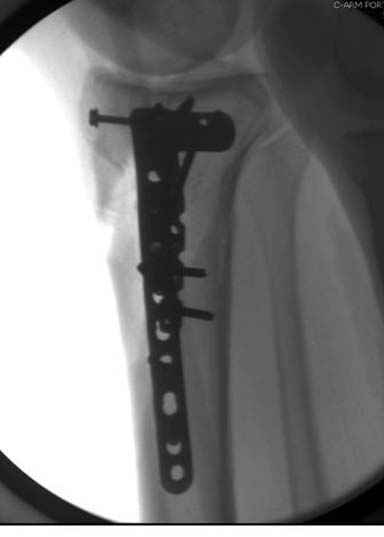

А нет ощущения, что плато "завалено" на варус?

293.jpg

21KB (22230 bytes)

Только вот линией вы вальгус показываете (норма)

Коллега, а нет ли снимков здоровой ноги, чтобы сравнить оси, если уж наши мнения разошлись?

Конечно, при таком повреждении всегда сложно выставить ось голени, знаю по собственному опыту, но все же?

Я думаю, что если с новыми, услышанными, например, от экспертов форума, оценками и размышлениями Вы вернётесь к изучению представленной Вами рентгенограммы, то увидите, что вы не восстановили ни плато, ни правильные осевые взаимоотношения. Вы оперировали на отёке, не в оптимальное время. Используя болты-стяжки, вы устроили то, что зачастую называют «костный сэндвич», такое сдавление кости много-много хуже для биологии, чем аккуратно введённая малоинвазивная вторая небольшая пластина с медиальной стороны. К тому же, и это чрезвычайно важно – ни пластина, ни заглублённый гвоздь не предотвращают здесь возможности развития вторичного варусного коллапса плато. А в условиях недостаточности опоры для медиальной суставной поверхности и латерально – ввиду отказа от пластики и отсутствия «рафтинга», слишком уж много «критических точек» нужно пройти данному пациенту. Я не знаю, куда это смотрят концы болтов стяжек? Или это гайки лежат внутрикостно? И прочая, прочая, прочая, что уже, впрочем, отмечено экспертами форума.